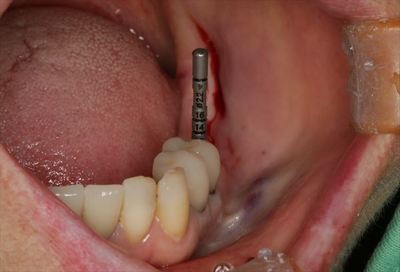

2本のインプラントを埋入しました。

ブルーのパーツは挿入ジグ=植えるためだけのパーツです。

挿入ジグを外しました。